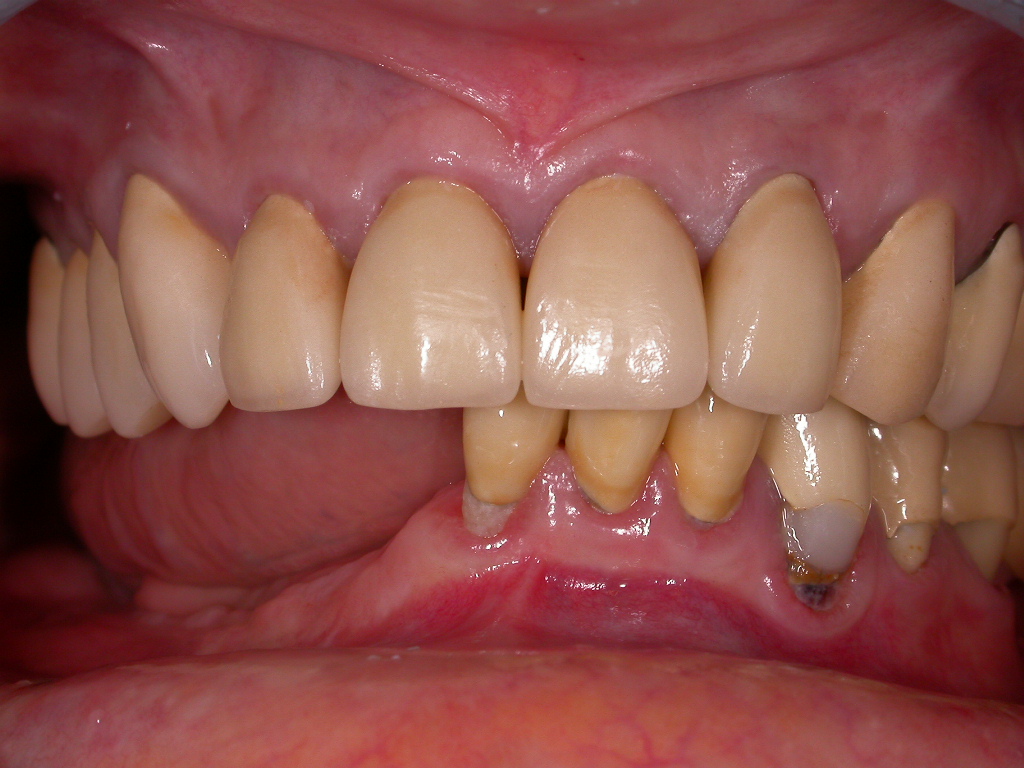

Unbefriedigende Ästhetik, vor allem aber Entzündungen im Knochen und eine massive Parodontitis mit bereits gelockerten Zähnen

Vorher: Unbefriedigende Ästhetik, vor allem aber Entzündungen im Knochen und eine massive Parodontitis mit bereits gelockerten Zähnen

Gesamtbehandlung in Sedierung: die Seitenzähne wurden durch Keramik-Implantate (Zahnentfernungen und Sofortimplantation) mit Knochenaufbau ersetzt; anschließend Gesamtüberkronung aus Vollkeramik mit Optimierung der Ästhetik

Nachher: Gesamtbehandlung in Sedierung: die Seitenzähne wurden durch Keramik-Implantate (Zahnentfernungen und Sofortimplantation) mit Knochenaufbau ersetzt; anschließend Gesamtüberkronung aus Vollkeramik mit Optimierung der Ästhetik